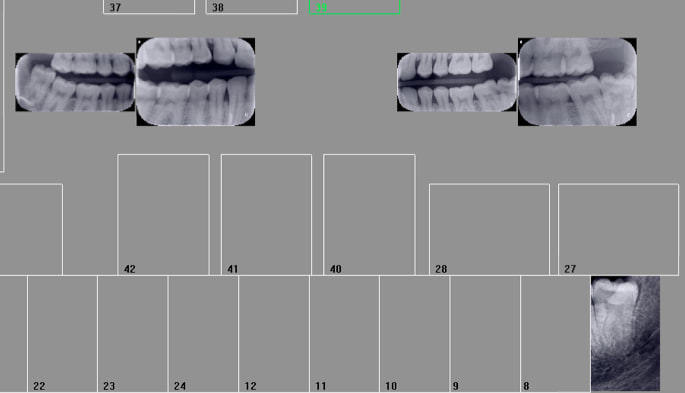

Ici on a du 2 du 3 en film agrémentés de quelques clichés de capteur RVG taille 1. -)

On va mélanger le nombre de radios, les formats et le nombre de secteurs pour noyer le poisson. Il y a une multitude d'emplacement libres sur mon FMS tuné. -)

Ca va ca va. de temps en temps on peine a à avoir les rebords alvéolaires because moins larges qu'un taille 2, mais dans l'ensemble c'est satisfaisant.

Tu as 4 secteurs dessus mais selon certains tu peux n'en compter qu'un alors que si tu utilises 2 taille 2 tu peux en compter 2 . Je suppose donc que si tu utilises 4 tailles 1 en vertical tu peux en compter 4. En suivant la logique hein ! -)

C'est moins net avec les tailles 3 je trouve notamment au niveau de l'os alvéolaire que tu es sensé avoir correctement. En taille 2 c'est plus propre. Ca double la dose de RX pour rien mais c'est plus propre. -)

Ca devient compliqué de coter sans tenir compte de la notion de secteurs quand on multiplie le format des films et qu'on mélange rétro coronaires et rétro alvéolaires, hein ? -)